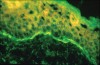

Diagnosis is based on previous history, clinical appearance, histologic examination, and direct immunofluorescence studies. Histopathologic features of OLP include hyperkeratosis, liquefaction degeneration of the basal cell layer of epithelium, saw-toothed or shortened rete ridges, and an intense band-like inflammatory infiltrate of predominate lymphocytes in the lamina propria with or without colloid bodies7 (Figure 4).

Figure 4  Histograph of lichen planus. Note the saw-tooth rete pegs.

Figure 4